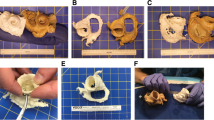

Among the partial errors, DEE as digital editing error is the least studied, while PrE as printing error is the most studied. Nevertheless, our results allow for an initial assessment of DEE in terms of its impact on the total error. The SegE was even studied significantly less often than the PrE, although the SegE seems to be much more influenced by manual input. When assessing the segmentation process, a distinction is made between publications in which the direct segmentation result was compared to the original structure (SegE) and those in which the segmentation was further processed (SegE+DEE), for example, using digital editing techniques such as smoothing. Analyzing the deviations in both groups, their values do not differ greatly. This may indicate that standard digital editing techniques such as smoothing or artefact removal could have a minor impact on the total error of the production process. This assumption is supported by results from Ionata et al. presenting the only available AMMD for the combination of digital editing error and printing error (DEE + PrE): with a value of 0.12 mm [157], it is close to the lower end of the range of values obtained for the isolated printing error (PrE). However, further research is needed to quantify the influence of DEE, as only three publications are found that individually address this error.

An accurate and realistic assessment of SegE can generally be defined as follows: A complex three-dimensional (anatomical) structure is surrounded by randomly arranged isodense structures during imaging. It is then segmented, and a 3D-scan of the original structure is compared with the direct segmentation result via surface comparison. Based on this definition, cadaver studies may not be the optimal method to evaluate SegE, considering the enormous efforts. To overcome these obstacles, future endeavours could focus on developing simple segmentation models that use artificial (3D-printed anatomical) structures and simulate adjacent (soft-) tissue.

Regarding combined errors, the combination of DEE and PrE has been studied the least, while the total error has been studied the most. Since the total error includes SegE, among others, similar challenges arise. Figure 7 illustrates methods for evaluating the total error that are found in the literature. They range from simple and inexpensive methods (e.g. scanning an artificial model in air combined with a comparison of linear measurements taken on the original structure and the printed model) to the current gold-standard (scanning of cadveric specimen, combined with a surface comparison between a 3D-scan of the original structure after dissection and a 3D-scan of the printed model). Besides cost, personnel and ethical aspects a limited availability has to be considered, too.

As a consequence, the need for alternatives seems justified. The combination of an artificial original structure with simulated adjacent tissue could be a promising solution that can be expected to achieve comparable accuracy and realism to cadaver studies but with significantly reduced cost and effort. Some attempts have been described in the literature to simulate adjacent tissue to increase the realism of the segmentation process [77, 156]. However, those still involve the use of cadaveric specimens: Van Eijnatten et al. embedded a human dry skull in silicone to simulate soft tissue for validating the influence of the head position during cone-beam CT [156]. Zhang et al. [77] placed artificial models of nasal airways inside a dry skull to use them as a realistic benchmark for the validation of their segmentation algorithm.